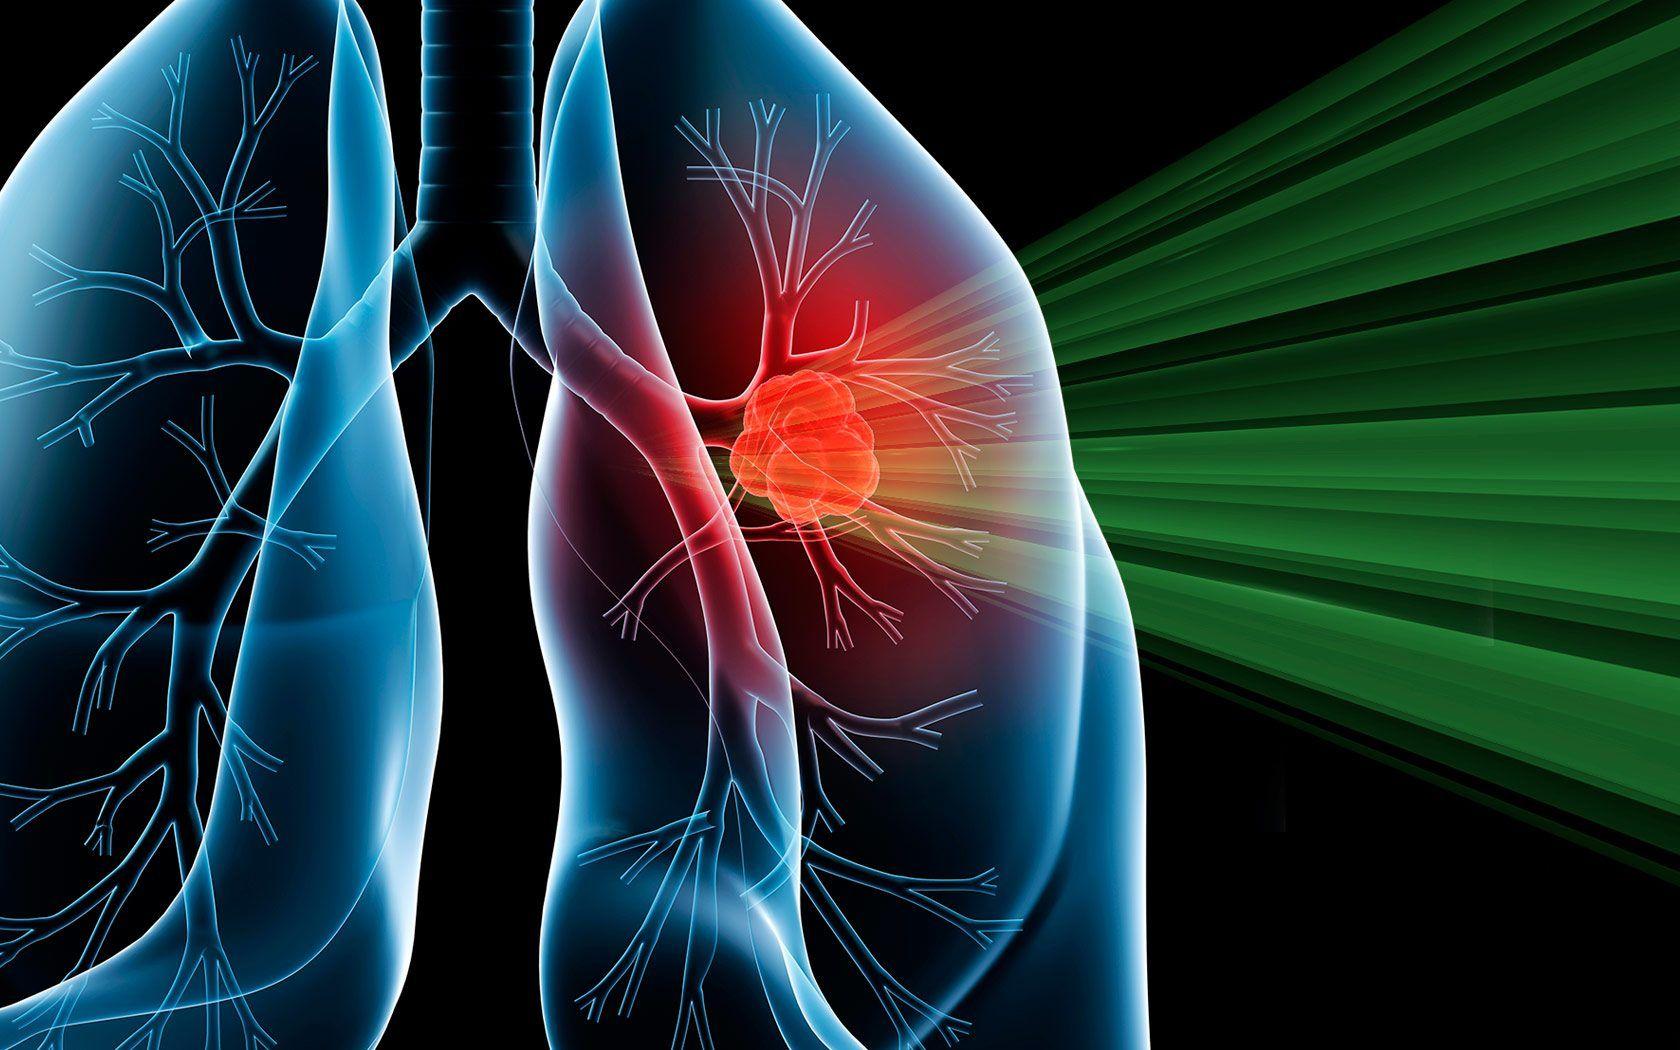

Lungs Wallpapers - Top Free Lungs Backgrounds - WallpaperAccess

wallpaperaccess.comlung lungs proton radiation chang wallpapers promise biomall wallpaperaccess imrt associate syngene senior

wallpaperaccess.comlung lungs proton radiation chang wallpapers promise biomall wallpaperaccess imrt associate syngene senior